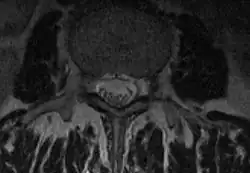

Als Duralsack oder Durasack wird im klinischen Sprachgebrauch der Schlauch aus harter Hirnhaut (Dura mater) bezeichnet, der das Rückenmark und die abgehenden Nervenwurzeln umgibt. Anatomisch ist diese Bezeichnung nicht völlig korrekt, da nicht berücksichtigt wird, dass auch die sogenannte Spinngewebshaut (Arachnoidea) an der Bildung dieser Umkleidung beteiligt ist. Der Duralsack endet auf Höhe des zweiten Sakralwirbels im Filum terminale.

Die Dura mater ist eine solide Hülle, die das hochempfindliche Nervengewebe des Rückenmarkes gegen mechanische Schäden schützen soll. Am Abgang der Nervenwurzeln bildet die Dura jeweils eine Ausstülpung, Wurzeltasche genannt, die die Nervenwurzel begleitet und erst dann in die bindegewebige Hülle des Nervs, das Epineurium, übergeht. Zudem ist der Duralsack mit Rückenmarksflüssigkeit (Liquor cerebrospinalis) gefüllt, auch hier wird eine Schutzfunktion, diesmal im Sinne eines Wasserkissens, angenommen.

Der Duralsack bietet eine recht einfache Möglichkeit, durch Punktion den Liquorraum zu erreichen. Die labortechnische Analyse der Rückenmarksflüssigkeit kann Aufschluss in Bezug auf die Diagnostik einer Reihe von Erkrankungen liefern. Genauso gut ist es aber auch möglich, ein Röntgenkontrastmittel in den Duralsack zu spritzen und damit Raumforderungen innerhalb des Spinalkanals, aber auch krankhafte Veränderungen an den Nervenwurzeln oder am Rückenmark selber festzustellen. Mit dem inzwischen erreichten hohen technischen Entwicklungsstand der Computertomografie und Kernspinresonanz-Diagnostik wird diese Röntgenkontrastdarstellung oder Myelografie immer seltener notwendig. Es ist auch gebräuchlich, Medikamente direkt in den Duralsack zu injizieren, als Möglichkeit, eine völlige Betäubung der unteren Körperhälfte zu erreichen (Spinalanästhesie), um hier Operationen durchführen zu können. In der Geburtshilfe wird meistens ein Betäubungsmittel nur in den Raum zwischen Dura und Wirbelkanal eingebracht (Periduralanästhesie).